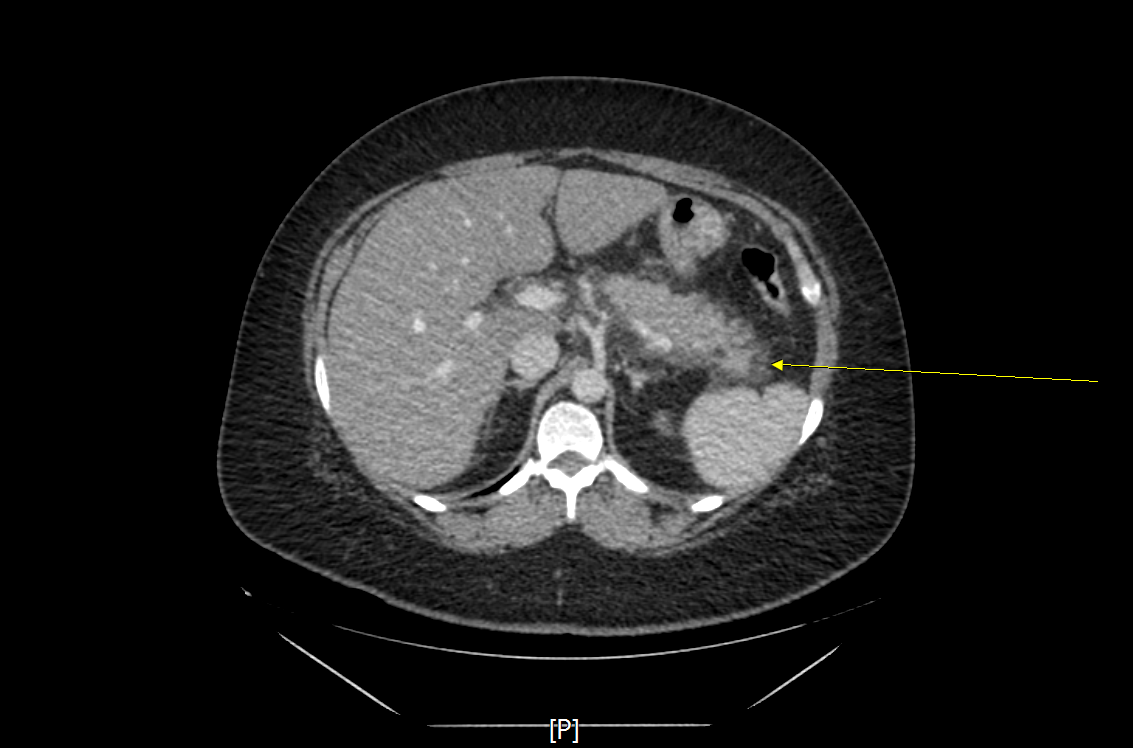

2-3. 영상검사에서 전형적인 소견

1) 복부 전산화단층촬영(CT), 자기공명영상(MRI), 복부 초음파(abdomen USG/SONO)

2) 복부 전산화단층촬영 : 급성 췌장염의 진단에 가장 중요한 영상검사로 혈청 amylase가 정상인 경우 췌장염의 진단에 필수적이다. 영상 소견을 통해 췌장의 괴사, 가성낭종(pseudocyst), 췌장성 복수와 같은 합병증도 함께 확인할 수 있어 유용하다.

3-2. 영상소견에 따른 분류

1) 간질성 부종성 췌장염 (interstitial edematous pancreatitis)

- 췌장괴사의 증거가 보이지 않은 췌장실질의 염증성 변화

- CT에서 조영제에 의한 췌장실질의 조영증가로 나타남.

- 국소 합병증으로 췌장 주변의 액체 저류 소견인 fluid collection과 낭종벽을 형성한 가성낭종(pseudocyst)을 형성키도 한다.

2) 괴사성 췌장염 (necrotizing pancreatitis)

- 염증으로 인한 췌장실질 및 췌장주위조직의 괴사

- 이미 괴사된 조직으로 조영제에 의해 조영증강 되지 않음.

- 국소 합병증으로 췌장 주변으로 궤사조직이 저류 되는 necrotic collection을 보이거나, 췌장괴사조직이 벽을 형성한 경우 walled-off necrosis소견을 보이기도 한다.

4-4. 복부 전산화단층촬영(Abdomen CT)

- 경증 췌장염에서는 불필요.

- 전형적인 증상 발생 4일 이내 시행하는 경우 타 질환으로 진단되는 경우는 거의 없으며, 괴사 여부, 합병증 여부 판정에 도움을 주지 않는다.

- CT를 시행해야 하는 경우

1) 췌장염의 진단이 불확실할 때

2) 중증(severe) 췌장염인 경우

3) 보존적 치료에 반응이 없거나 악화되어 중재 치료(Intervention)가 필요한 경우

- 가능하면 췌담도 질환에 대한 변별력을 높이기 위해 arterial, portal, venous phase를 촬영하는 3-phase CT의 촬영을 추천함.